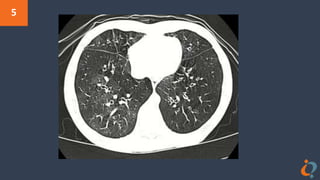

Bronchiolitis obliterans(BO) is a disease that results in obstruction of the smallest

airways of the lungs due to inflammation.Symptoms include a dry cough,

shortness of breath, wheezing and feeling tired. This disease is also called X Lung

because workers at a factory that packaged X were found to have bronchiolitis

obliterans more often than other people. It was later discovered that the chemical

that caused this condition its nickname was diacetyl which gave X its rich, buttery

scent. Most companies immediately stopped using diacetyl as a flavoring but it's

still used in many e-cigarette flavors. Cigarettes destroying lungs, what’s new?

Adjoining picture of a high resolution CT scan of lungs with BO could be a clue to

X. Give X.